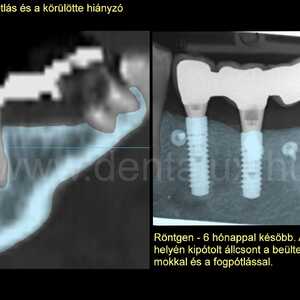

Lépésről lépésre: egy komplex fogimplantátum és csontpótlás története Kecskeméten. Nézze meg, hogyan spóroltunk hónapokat páciensünknek 3D tervezéssel!

Egy komplex fogpótlás története – az alapoktól az új mosolyig Nagy örömmel számolunk be egy különleges, komplex fogimplantátum-csontpótlás-fogpótlás ellátásunkról, amit nemrég fejeztünk be. Büszkék vagyunk…